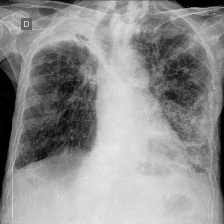

We produce localization maps by computing Ablation-CAMs for our models, applied to over 100 images from the COVIDx test split. These maps highlight image regions deemed important by the model for classifications. Figures 2(a) and 2(b) show three example COVID-positive images and localization maps computed on the Swin-B model (200-epoch). Figure 2(c) shows corresponding maps produced by the ResNet-50 baseline model on the same images.

The localization maps produced by Swin Transformers highlight the lung area, successfully focusing on the ground glass pattern, consolidation and peripheral linear opacities used by human doctors for diagnosis (Cleverley et al., 2020). In contrast, maps produced by the ResNet-50 are less successful, highlighting irrelevant areas such as shoulders and arms, sometimes missing the lungs entirely.